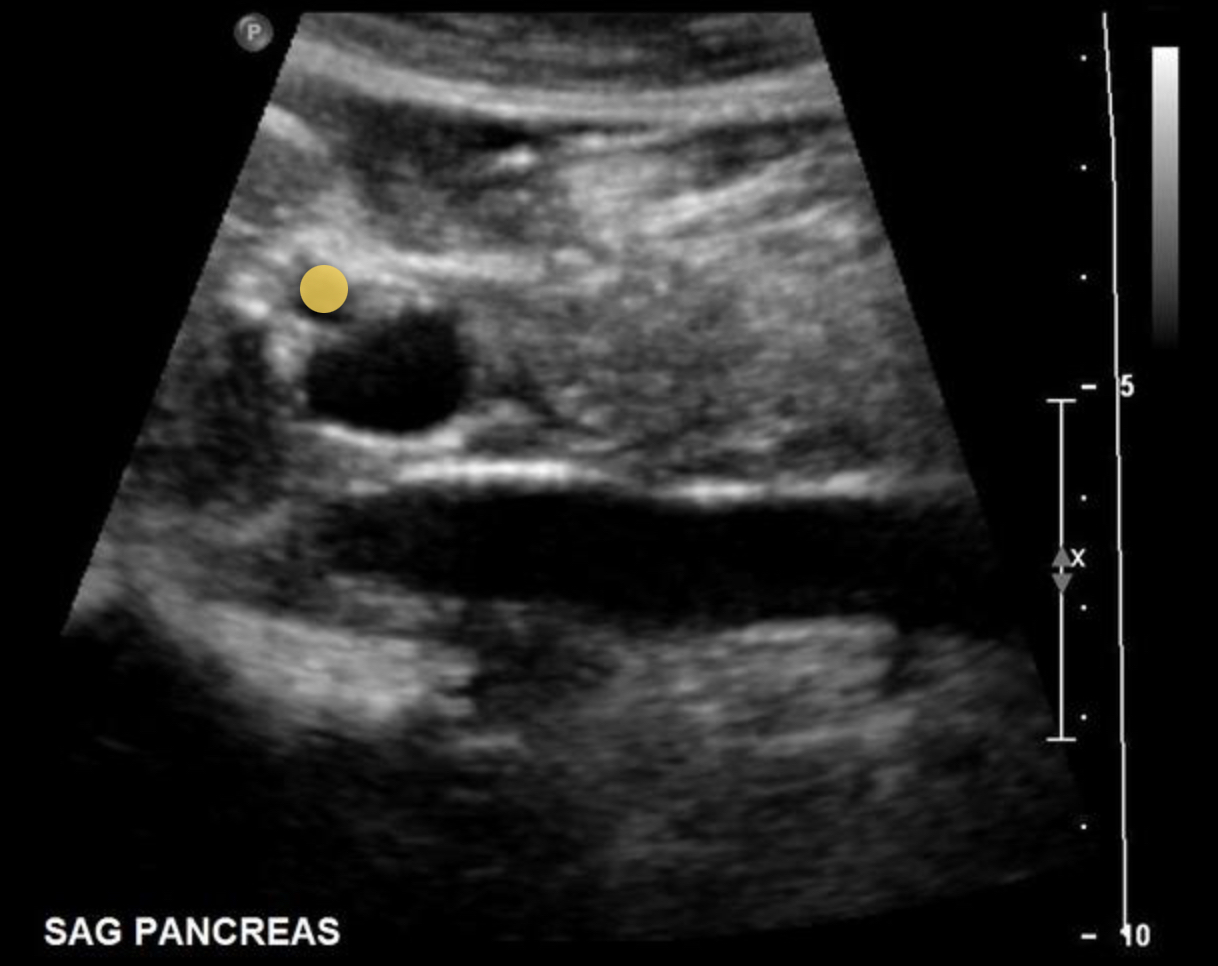

What structure is indicated by the purple circle?

Portal triad

What structure is marked with the X on the image?

Main pancreatic duct